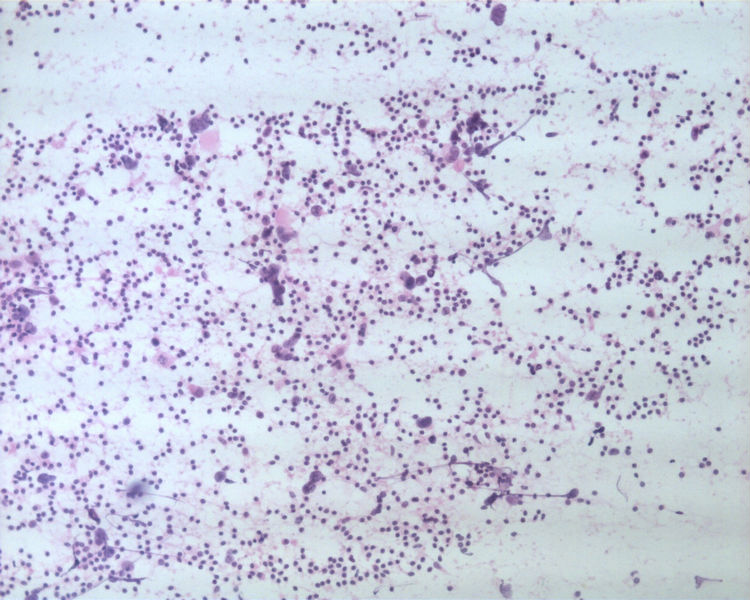

男性,50岁,右锁骨上淋巴结穿刺。

• 男性,50岁,右锁骨上淋巴结穿刺。图1

淋巴结转移性的大细胞神经内分泌癌

细胞块的细胞成分多且有成团趋势,加上IHC支持肺来源的大细胞神经内分泌癌转移至颈部淋巴结。

结合细胞腊块及免疫组化结果,诊断了淋巴结转移性的大细胞神经内分泌癌。